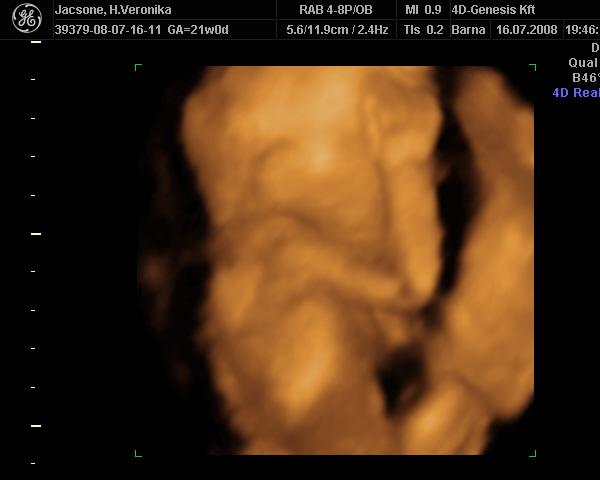

Képzeljétek, tegnap épp a Lotz Károly utcában jártam, és elcsábultam egy 4D-re :) Noel nagyon tündéri volt. Folyton a kukiját mutogatta :D Már 658 g!!! Nem sok az egy kicsit? Bár épp tele volt a pocija :)

Teszek fel két képet. A kis kéz-láb csomagos a kedvencem. Még a pici pofiját is lehet látni :)

Kép Kép

Mi vasárnap voltunk újabb 4D-n, most már bizonyossággal mondták, hogy kisfiút várunk. Meg tudtam azt is, amit eddig nem értettem, hogy miért van ekkora minőségi különbség 4D és 4D között... A válasz a magzatvíz mennyiségében rejlik, a szaki elmondása szerint, minél több víz van jelen, annál kontúrosabb, élesebb a kép. Végülis logikus, de erre sosem gondoltam.